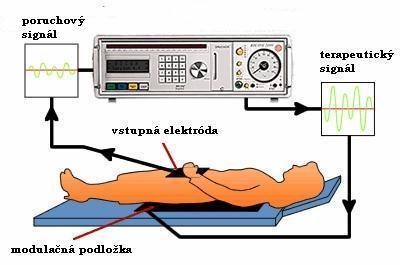

A világegyetemben minden elektromágneses rezgésekből áll, mi magunk is. Ha a rezgések harmonikusak, akkor, egészségesek vagyunk. Amennyiben ez a harmónia felborul, az testi és/vagy lelki betegségeket okozhat. Ha valaki képes a test a frekvenciáját 62 MHz felett tartani, akkor nem kell aggódnia, hogy megbetegszik. Módszerek a rezgés emelésére.

Minden szervünknek és a bennük lévő sejteknek egyedi, csak rájuk jellemző rezgése (frekvenciája) van. Egy beteg szerv működése javítható, ha a rá jellemző optimális frekvenciákat juttatjuk hozzá. Az átadott helyes rezgés fenntarthatósági ideje. A biorezonancia célja, hogy kis elektromos hullámok segítségével visszaállítsuk az eredeti állapotot. Mit jelent a magnetoterápia? BioHarmonex készülék. Vizsgálatok és terápia BICOM készülékkel. A Biokom készülék előnyei. SENSITIVE AUDIT 550 típusú készülék (ábra)..

Minden szervünknek és a bennük lévő sejteknek egyedi, csak rájuk jellemző rezgése (frekvenciája) van. Egy beteg szerv működése javítható, ha a rá jellemző optimális frekvenciákat juttatjuk hozzá. Az átadott helyes rezgés fenntarthatósági ideje. A biorezonancia célja, hogy kis elektromos hullámok segítségével visszaállítsuk az eredeti állapotot. Mit jelent a magnetoterápia? BioHarmonex készülék. Vizsgálatok és terápia BICOM készülékkel. A Biokom készülék előnyei. SENSITIVE AUDIT 550 típusú készülék (ábra)..